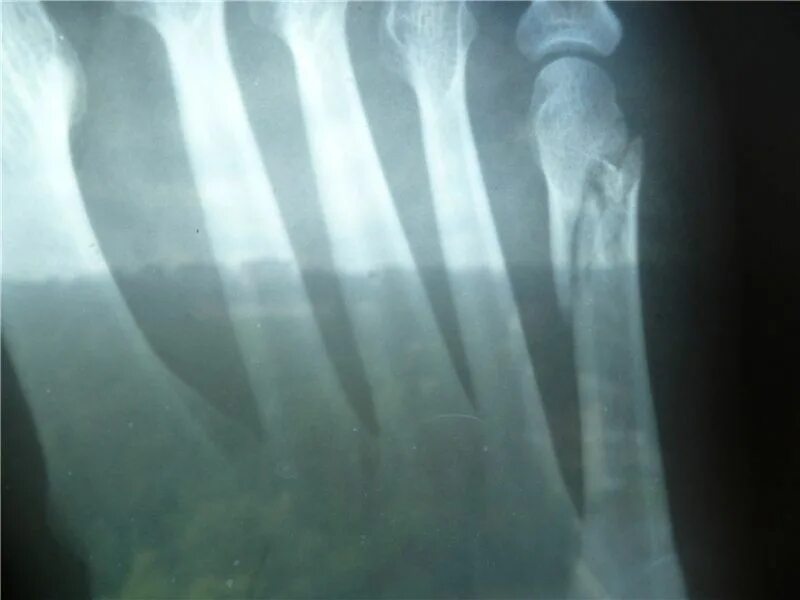

Что делать чтобы перелом быстрее сросся